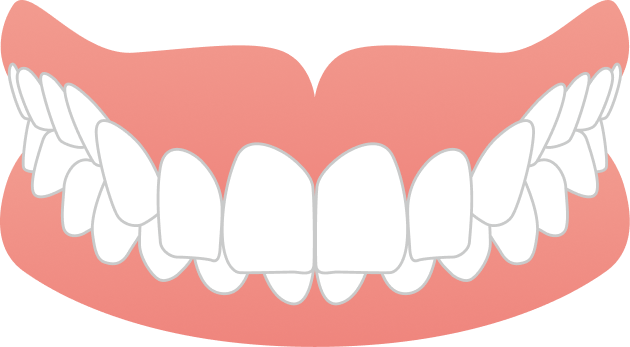

AFTER

治療期間は1年8ヶ月で、大学生のうちに治療を終えることができました。見た目の改善だけでなく、噛み合わせも整い、前歯でしっかり噛めるようになっています。

| 年齢・性別 | 20代女性 |

|---|---|

| 主訴 | 前歯のガタガタと噛み合わせが気になる |

| 施術内容 | 歯全体のマウスピース矯正システム「インビザラインフル」を用いた治療 |

| 治療期間 | 1年8ヶ月 |

| 費用 | 924,000円(税込) |

| リスク/副作用 | 全ての方で、疼痛、咬合痛、歯根吸収、歯肉退縮、歯髄壊死が生じる可能性があります。 |

| その他注意点 | 指定した時間、マウスピースをつけていただけない場合は治療期間が長くなる場合があります。 |